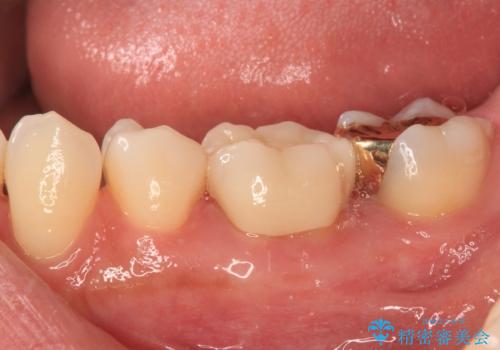

- 奥歯のむし歯処置を行っていたものの、しみて痛みが続く状態での経過観察が続いていたため、転院を希望して来院された患者様です。

痛みが続いているとのことで、むし歯が神経組織に及んでいる可能性があるため、処置を行うに当たりラバーダムによる唾液の排除を行うこととしました。

手前の歯はむし歯の範囲が広いためオールセラミッククラウンにて、最後方歯は部分的なむし歯であったのでPGAインレー(プラチナゴールドインレー)にて治療を進めることとしました。